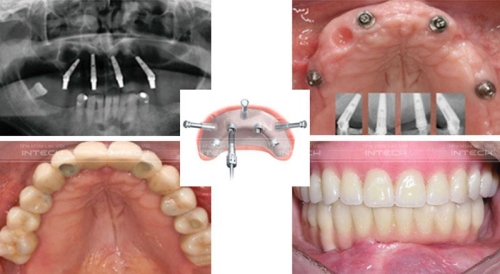

Trồng Răng Implant Nguyên Hàm: 6 Bí Mật Khủng Khiếp

Cô chú anh chị cũng biết là, để cấy ghép Implant, bác sĩ sẽ cấy 1 trụ vào vị trí mất răng để thay thế chân răng thật. Trụ này sẽ phải đảm bảo có lớp bề mặt giống như xương người để có thể tích hợp tốt với xương hàm. Sau khoảng 1-3 tháng tích hợp, bác sĩ sẽ lắp răng Implant hoàn thiện để đáp ứng ăn nhai cũng như thẩm mỹ. Tuy nhiên, đó là áp dụng với trồng răng Implant đơn lẻ? Vậy với Implant nguyên hàm nó có khác biệt gì khôn